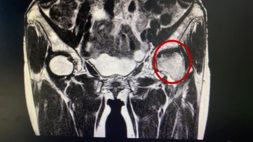

- 近日,漳州市中医院骨伤科成功实施了股骨头坏死“带血管蒂腓骨骨移植术”,为早中期股骨头坏死患者带来福音。 接受手术的林女士,52岁,半年前开始出现左髋部疼痛,活动时疼痛加重,在外院治疗效果不好。经多方打听,得知我院骨伤科是国家临床重点专科,对这类疾病的治疗很有经验,反复权衡后决定到我院求诊。 骨关节专家林石明副院长及其医疗小组成员,经过反复研究患者的核磁共振及CT三维血管重建等资料后,考虑为左侧股骨头坏死,程度在二期到三...发布时间:2021-03-19